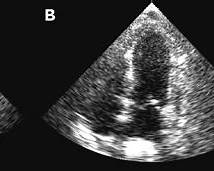

Takotsubo cardiomyopathy is an acute, reversible form of heart failure characterized by transient left ventricular systolic dysfunction, often triggered by intense emotional or physical stress, and mimicking acute coronary syndrome without obstructive coronary artery disease.

Diagnosis is based on clinical presentation, ECG changes, modest troponin elevation, echocardiographic regional wall motion abnormalities beyond a single coronary territory, absence of obstructive coronary disease, and supportive cardiac MRI findings.

Most patients recover left ventricular function within weeks to months, although acute complications such as cardiogenic shock, arrhythmias, and thromboembolism may occur during the initial phase.